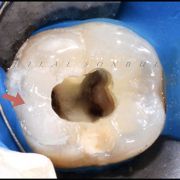

Based on evidence, all posterior teeth should be restored with cuspal coverage after root canal treatment. However, most of these teeth are badly destructed due to caries or large existent restoration. The key of success is to preserve the remaining tooth structure and restore the tooth conservatively. Dr khalid Merdad and I worked simultaneously to accomplish this task.